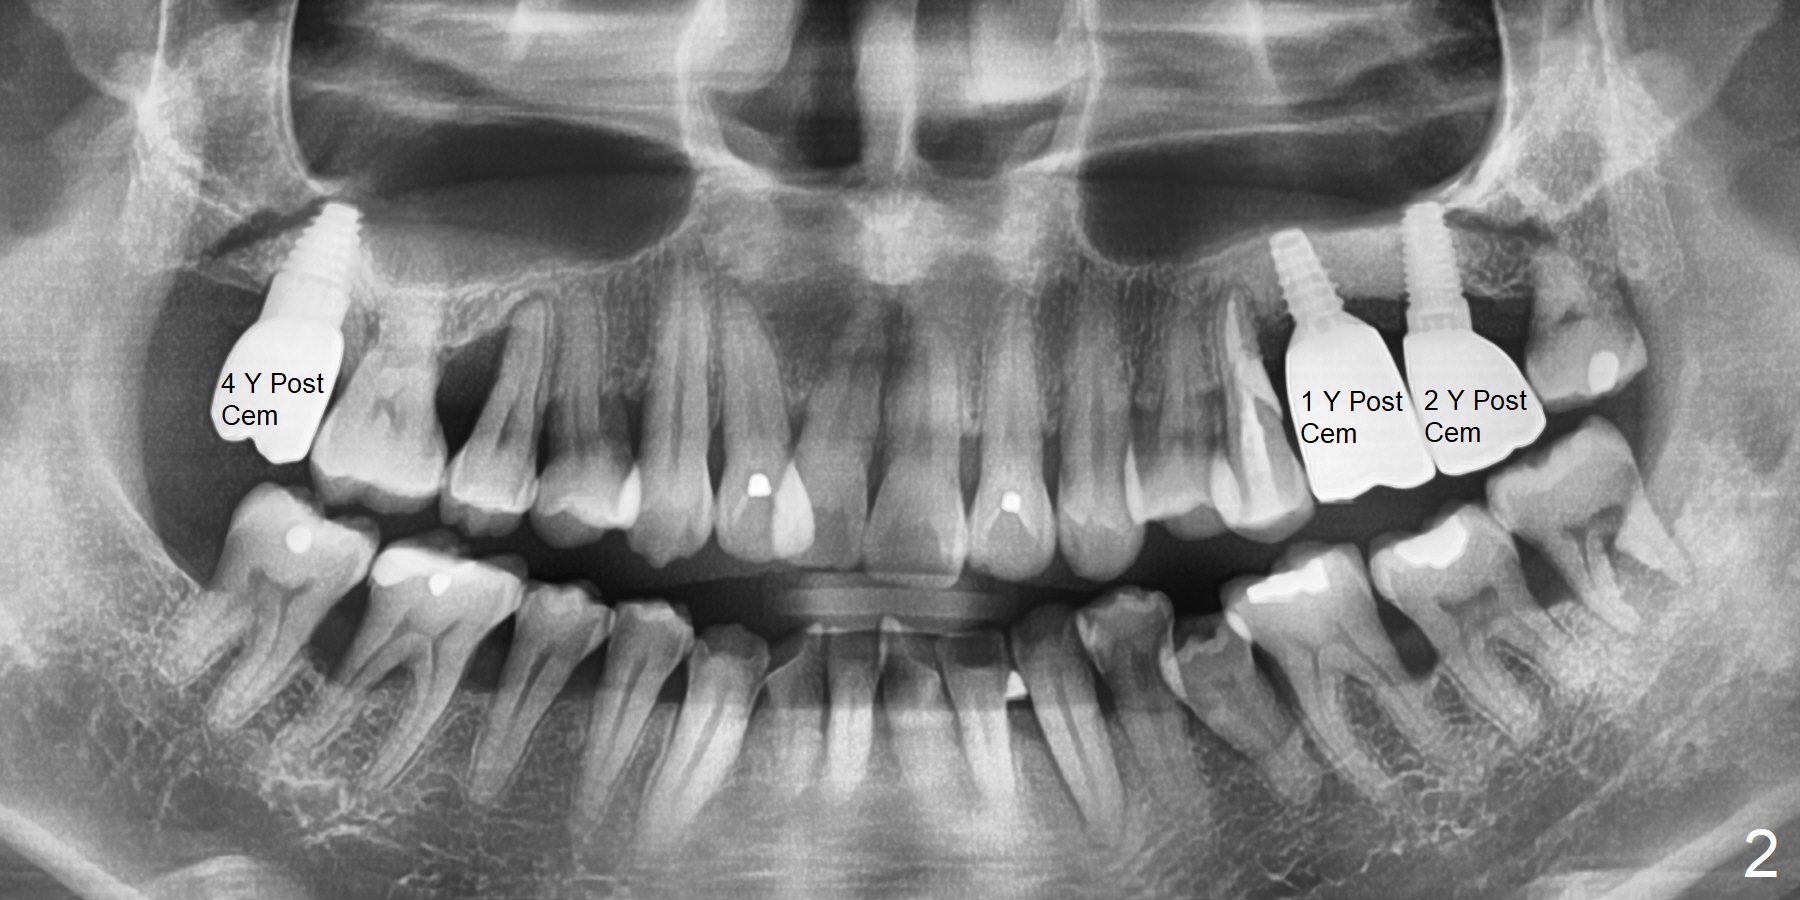

When a 38-year-old man presented to the office 10 years ago, there were 2 missing teeth #2 and 14 with 5.8 mm and 1 mm bone height, respectively (Fig.1). Later the tooth #15 was extracted. A 6x11 mm implant was placed with internal sinus lift at #2 first. Two of 5x11 mm tissue-level implant were placed with lateral window sinus lift at #14,15. The implant at #14 is loose 3 months post cementation and dislodges later. Four months post bone graft, a 5x7 mm IBS implant was placed with CMC technique. With progressive loading at #14, the crown functions 1 year post cementation with the thick bone (Fig.2 *).